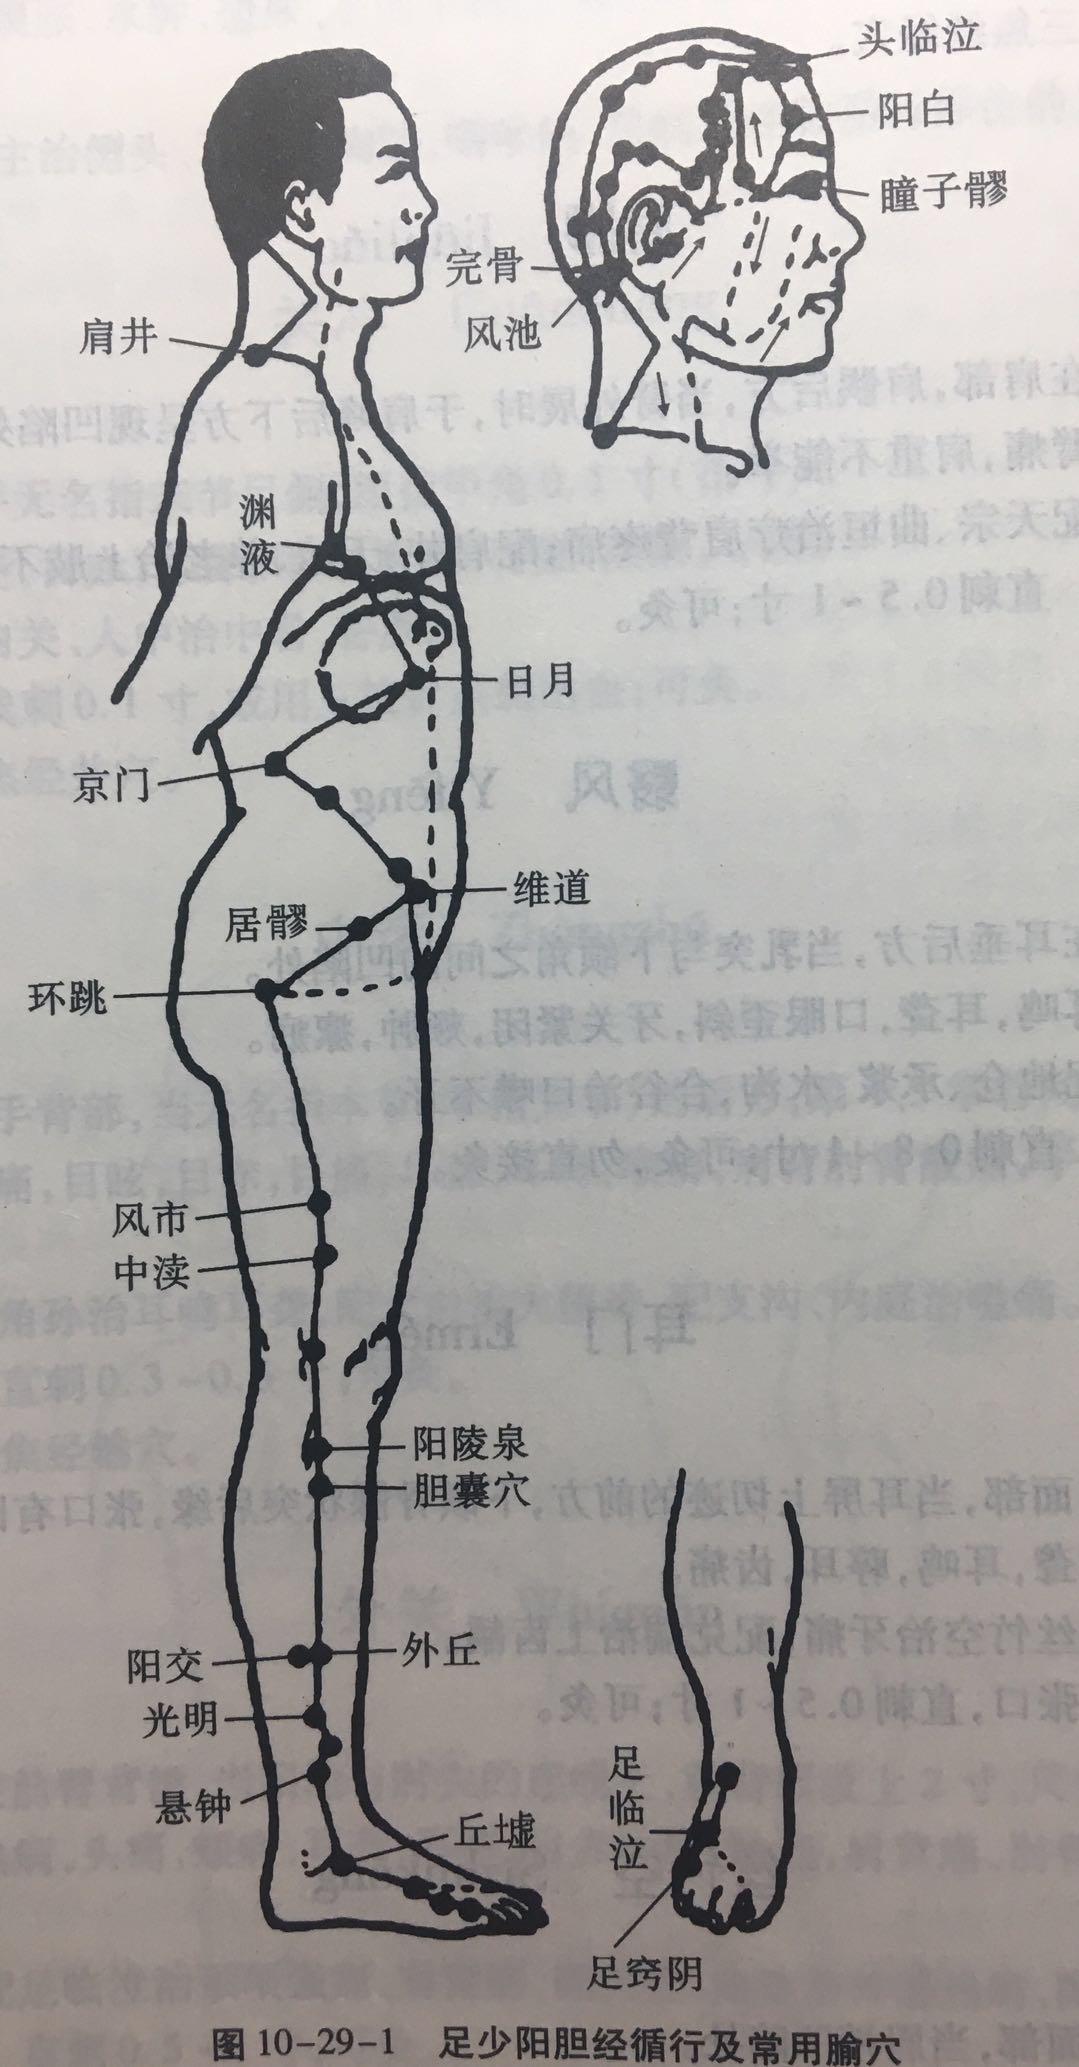

【(十一)足少阳胆经(图 10-29-1)】

1、时辰 子时 23 ~ 1

2、歌诀 少阳足经瞳子髎,四十四穴行迢迢,听会上关颌厌集,悬颅悬厘曲鬓翘,率谷天冲浮白次,窍阴完骨本神邀,阳白临泣木窗辟,正营承灵脑空摇。风池肩井渊腋部,辄筋日月京门标,带脉五枢维道续,居髎环跳风市招,中渎阳关阳陵泉,阳交外邱光明宵,阳辅悬钟邱墟外,临泣地五会侠溪,第四指端窍阴毕。

3、经脉循行 起于目外眦(瞳子髎),向上到额角,返回下行至耳后,沿颈部向后交会大椎穴,再向前入缺盆部,入胸过膈,联络肝脏,属胆,沿胁肋部,出于腹股沟,经外阴毛际,横行入髋(kuān)关节(环跳)。

耳后支部:从耳后入耳中,出走耳前,到目外眦处向后向下经颊部会合前脉与缺盆部。下行腋部,沿侧胸部,经季肋和前脉会于髋关节后,再向下沿大腿外侧,行于足阳明和足太阳经之间,经腓(féi)骨前直下到外踝前,进入足第 4 趾外侧端(足窍明)。

足背部支脉:从足临泣处分出,沿第 1、2跖骨之间,至大趾端(大敦)与足厥阴经相接。

4、主要病候 口苦、目眩、疟疾、头痛、颌痛、目外眦痛、缺盆部、腋下、胸胁、股及下肢外侧、足外侧痛等。

5、主治概要 主治侧头、目、耳、咽喉病、神志病、热病及经脉循行部位的其他病证。

瞳子髎(liáo)

【附注】 手太阳,手、足少阳之会。

阳白

【附注】 足太阳、阳维之会。

头临泣

【附注】 足太阳、少阳、阳维之会。

风池

【附注】 足少阳、阳维之会。

肩井

【附注】 足少阳、阳维之会。

环跳

【附注】 足少阳、太阳二脉之会。

风市

【刺灸法】 直刺 1 ~ 1.5 寸;可灸。

阳陵泉

【附注】 足少阳经合穴;胆的下合穴;八会穴之筋会。

光明

【附注】 胆经络穴。